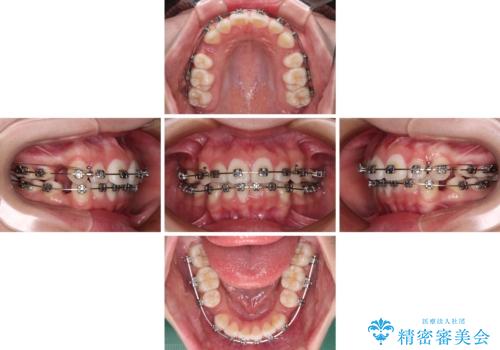

前歯のデコボコとクロスバイトを治したい ワイヤー装置による抜歯矯正

- 歯のデコボコや八重歯、クロスバイトを気にして来院された患者様です。

上下左右第一小臼歯4本を抜歯し、ワイヤー装置にて歯列を整え、さらには少しでも口元を引っ込めるよう矯正治療を行うこととしました。

上下の骨格での左右差が小さかったことと、抜歯矯正であったことで、上下正中の位置をきれいに合わせることができました。